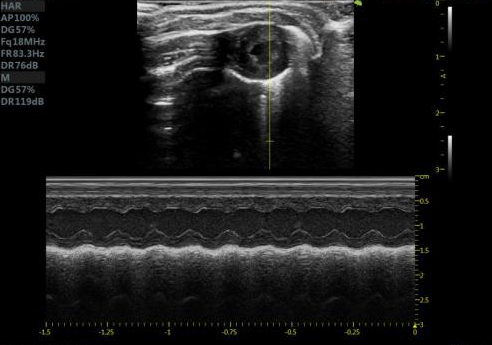

大鼠短轴M型 大鼠长轴M型

大鼠长轴B型 大鼠主动脉弓